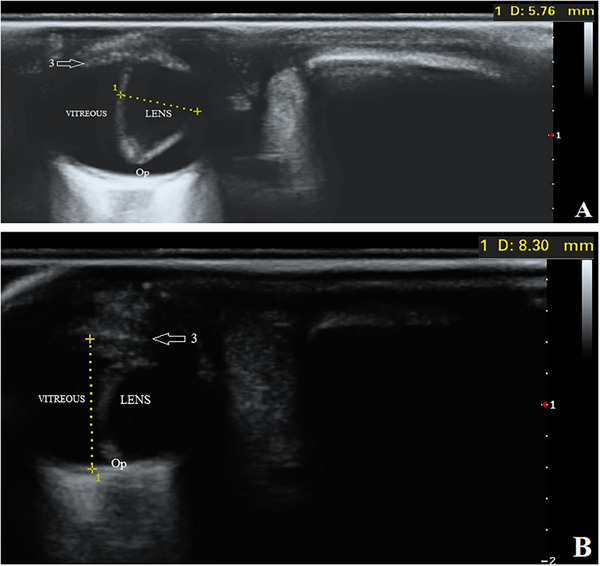

先天性眼睛畸形是不常见的,在一些犬种,没有证据表明他们的发生。本报告旨在描述中亚牧羊犬复杂小眼症的临床和超声表现。本文介绍了两窝3只2个月大的雌性中亚牧羊犬幼犬,因其主人自诉出生后眼睛异常而被转介至我院教学医院。临床检查幼犬反应灵敏,生命体征正常,未见其他结构异常。在所有三只狗的眼科评估中,球体出现双侧小且凹陷在眼眶中。在幼犬眼睛的超声波中,晶状体厚度和眼球轴向长度分别大于和小于同一年龄和品种的健康幼犬的眼睛测量值。此外,在所有三只小狗中,晶状体位于玻璃体腔内,并垂直于其自然轴移位。在此基础上,诊断为双侧复杂性小眼和先天性晶状体异位两种病因不明的眼部畸形。由于这种畸形可能与犬舍内的高度近亲繁殖以及环境和遗传因素有关,这些情况可以通过育种努力和育种前筛选计划加以限制。

Congenital eye malformations are uncommon and in some dog breeds, there is no evidence of their occurrence. This report aimed to describe the clinical and ultrasonographic findings of complex microphthalmia in Central Asian Shepherd dogs. Three 2-month-old female Central Asian Shepherd puppies from two litters were referred to our teaching hospital with the owner's complaint of eye abnormalities since birth. The puppies were alert on clinical examination, the vital signs were normal, and no other structural abnormalities were observed. In the ophthalmological assessments of all three dogs, the globe appeared bilaterally small and sunken in the orbit. In the ultrasound of the puppies' eyes, the lens thickness and axial length of the globe were greater and less than the values measured in the eyes of a healthy puppy of the same age and breed, respectively. Moreover, in all three puppies, the lenses were located in the vitreous chamber and displaced perpendicular to their natural axis. On the basis of this, bilateral complex microphthalmia and congenital ectopia lentis, two ocular malformations of unclear etiology, were diagnosed. Due to the possibility of an association between such malformations and a high grade of inbreeding in kennels, as well as environmental and genetic factors, these conditions can be limited by breeding efforts and pre-breeding screening plans.